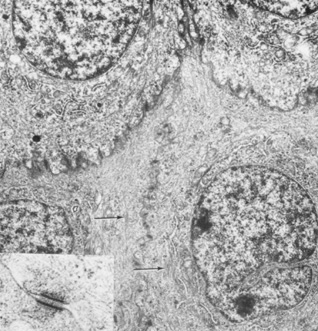

The human corneal endothelium is a single layer of 400,000 to 500,000 cells. Confocal microscopy provides views of this cell layer that surpass the details seen under specular microscopy (Figs. 19 and 20). Cells are 4 to 6 μm in height and 20 μm in width, and their posterior surfaces are predominantly hexagonal when viewed under specular microscopy (Fig. 21). Cross-sectional views with electron microscopy show that cell lateral walls are extremely tortuous and interdigitate with extensive folds and finger-like projections. It has been estimated that the total paracellular path length may be 10 times longer than the total height of the cell.90 Numerous gap junctions along the lateral membranes provide cell-to-cell cytoplasmic communication as evidenced by the presence of connexin 43 and the spreading of fluorescent dye from an injected cell to surrounding cells (Fig. 22).91

The apical portion of the lateral cell membranes facing the anterior chamber possesses small flap-like or leaflet-like features that overlap adjacent cells and harbor segmented tight junctions that form an incomplete seal around the apical cell margin (Fig. 23). Megamolecules (greater than 80 kd) are essentially prevented from penetrating the paracellular pathway, but molecules such as horseradish peroxidase and lanthanum are able to cross the apical junctions.92,93 While these tight junctions appear dimensionally larger than those found in the apical cells of the epithelium, they are not as efficient.90 Nevertheless, these junctions, combined with the closely apposed paracellular pathway, prevent excessive passive transport of anterior chamber fluid into the stroma. Any normal leakage that may occur around the endothelial cells tends to be counterbalanced by the active ion transport processes in the cell membranes. With pathologic cellular damage or substantial reduction in cell density from a normal value between 1,400 and 2,500 cells/mm2 to a critical value of approximately 400 to 700 cells/mm2, the endothelial transport capability becomes overwhelmed, and chronic stromal edema can ensue.90 Endothelial cell density normally increases from the center to peripheral cornea by approximately 10%, with the superior peripheral quadrant increasing by nearly 16%.94

Fig. 23. Extensively interdigitated lateral membranes of endothelial cells. Near the apical margin, a tight junction is formed (arrow). Bar = 0.5 ×m. (Courtesy of Drs. Rodrigues, Waring, Hackett, and Donohoo.)